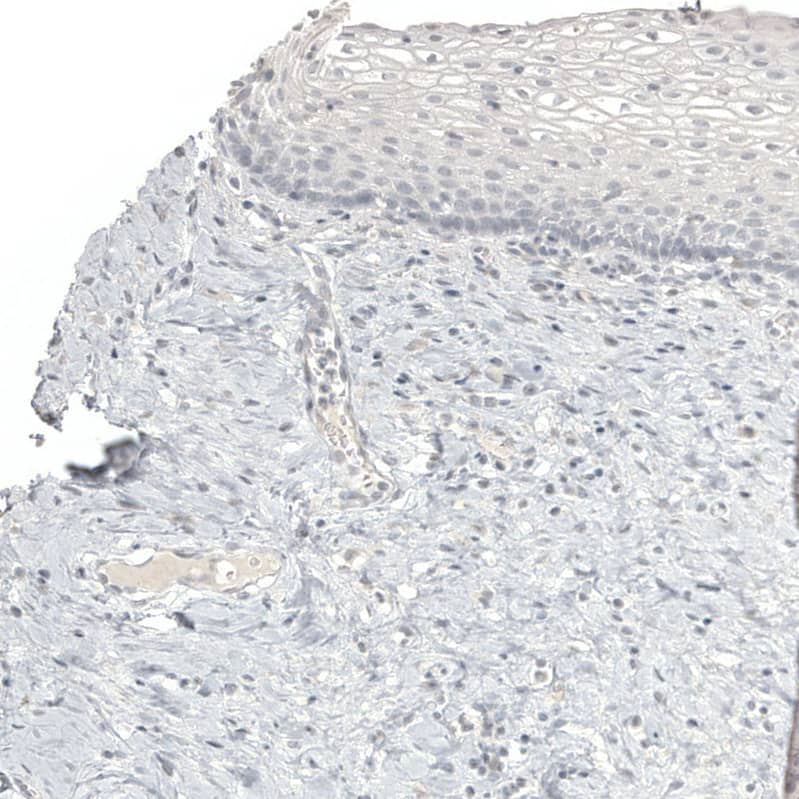

Staining of human cervix shows no positivity in squamous epithelial cells as expected.

Staining of human prostate shows no positivity in glandular cells as expected.